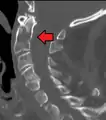

- A fracture of the base of the dens as seen on CT